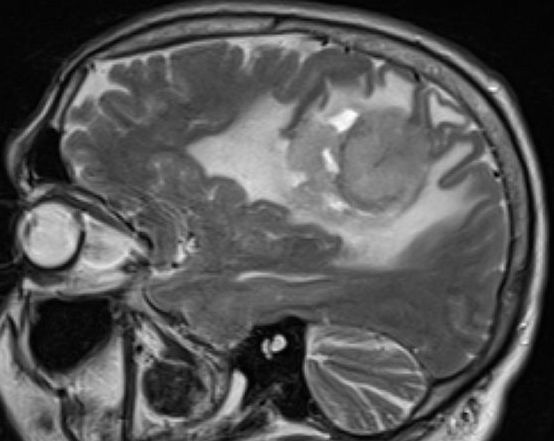

59jähriger Mann, bei dem Gangstörungen auffielen. Histologisch primär zerebrales aggressives T-Zell-Lymphom.![]() | |||